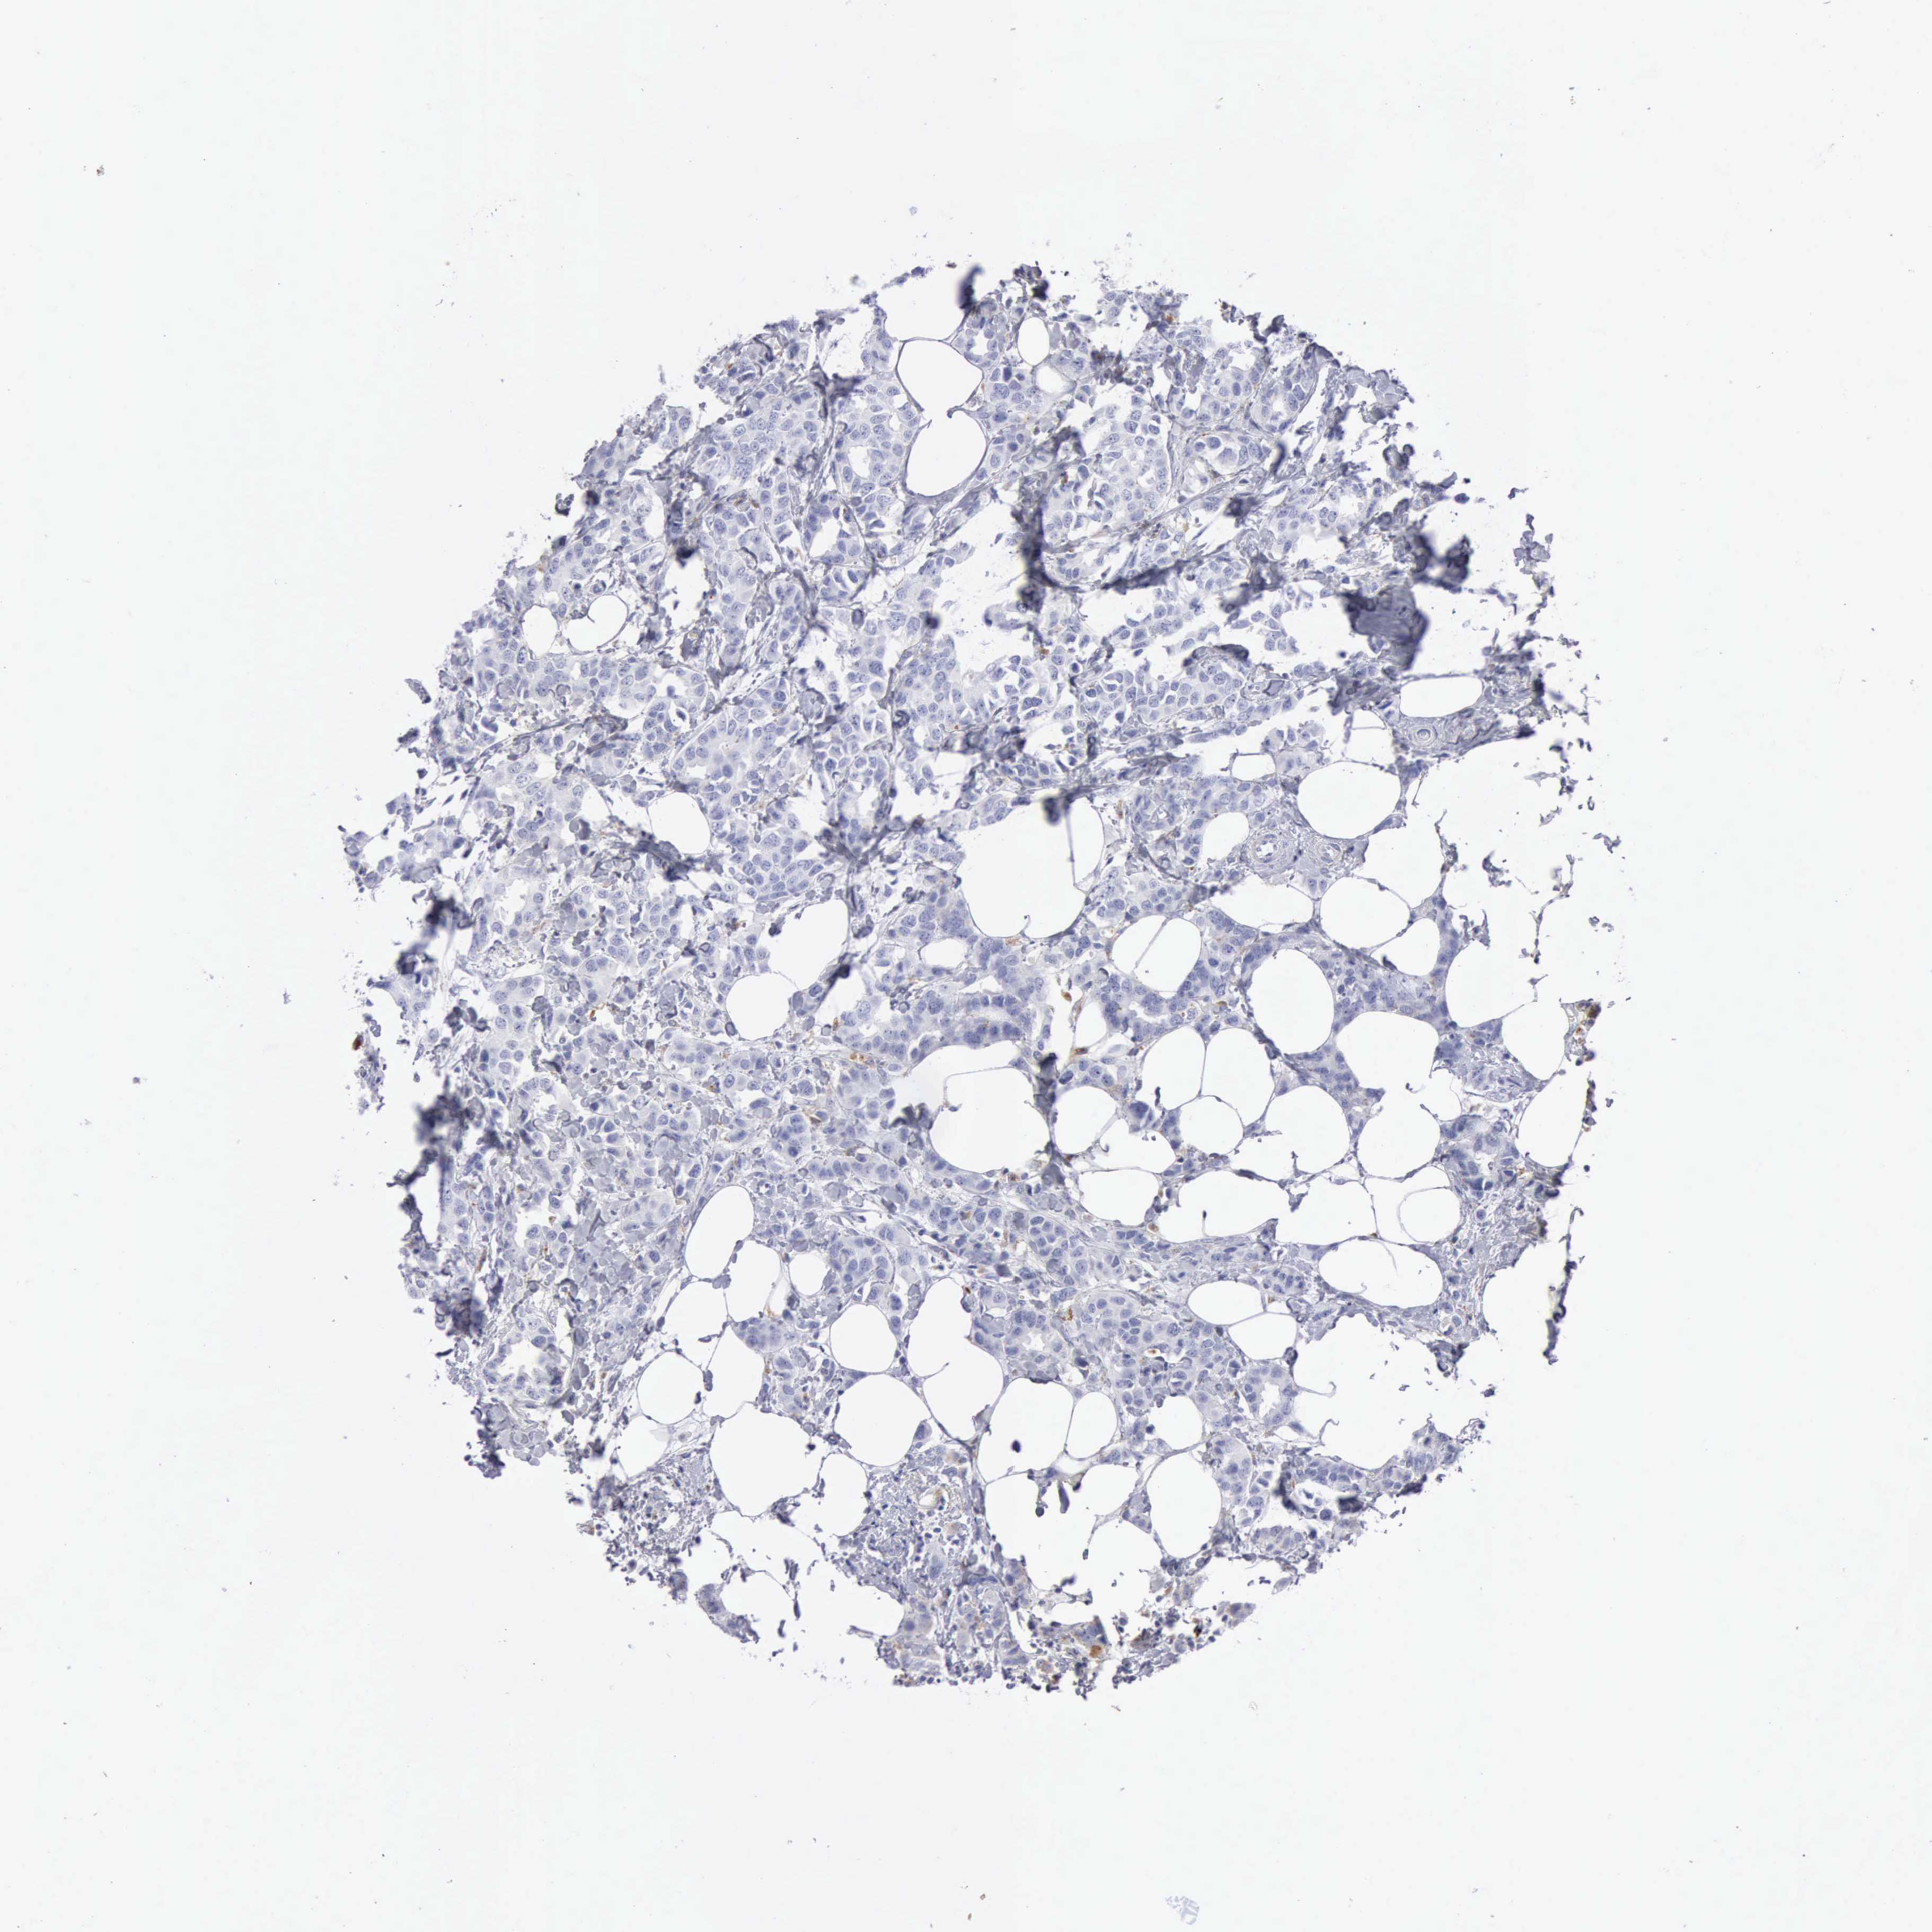

BRCA TCGA BRCA VALIDATION PROTEIN EXPRESSION

Breast cancer

Human cancer